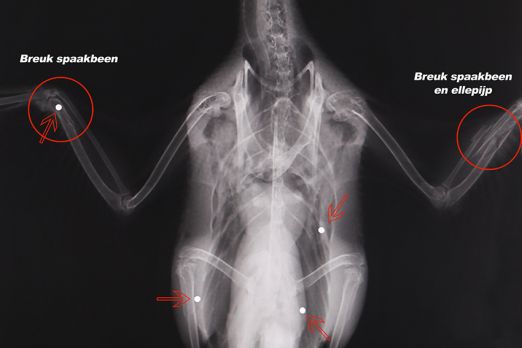

De zoektocht naar de geschoten zaagbek was succesvol. Er werd een vrouwelijke vogel terug gevonden. De röntgenfoto die in het Natuurhulpcentrum  werd gemaakt is duidelijk: de vogel zit vol met hagelbolletjes. Twee gebroken vleugels en een gebroken poot was het verdict. De zaagbek wordt ondertussen gestabiliseerd en de dierenartsen bekijken momenteel de mogelijkheden tot operatie, maar de verwondingen zijn bijzonder ernstig.